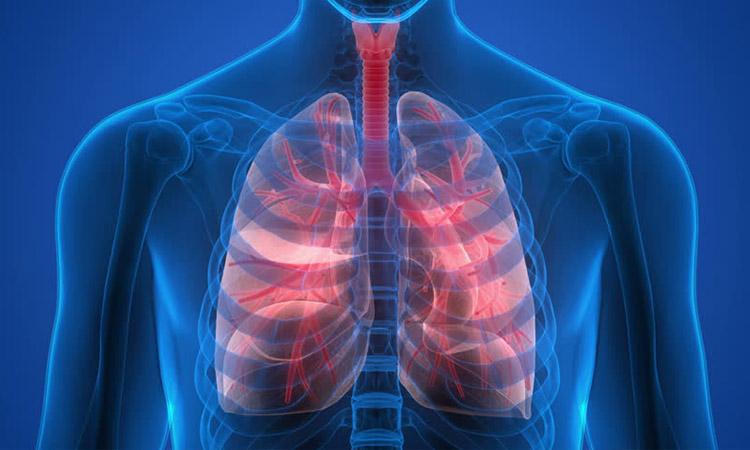

When we inhale isolated coronavirus particles, more than 65 per cent reach the deepest region of our lungs where damage to cells can lead to low blood oxygen levels, new research has discovered.

The study, led by the University of Technology Sydney researchers, found that more of these aerosols reach the right lung than the left.

While previous research has revealed how virus aerosols travel through the upper airways including the nose, mouth and throat, the study published in the journal Physics of Fluids was the first to examine how they flow through the lower lungs.

"Our lungs resemble tree branches that divide up to 23 times into smaller and smaller branches. Due to the complexity of this geometry it is difficult to develop a computer simulation, however we were able to model what happens in the first 17 generations, or branches, of the airways," said lead author Saidul Islam, from the varsity.

"Depending on our breathing rate, between 32 per cent and 35 per cent of viral particles are deposited in these first 17 branches. This means around 65 per cent of virus particles escape to the deepest regions of our lungs, which includes the alveoli or air sacs," he added.

The study also revealed that more virus particles are deposited in the right lung, especially the right upper lobe and the right lower lobe, than in the left lung. This is due to the highly asymmetrical anatomical structure of the lungs and the way air flows through the different lobes.

The research is backed up by a recent study of chest CT scans of Covid-19 patients showing greater infection and disease in the regions predicted by the model.

The team modelled three different flow rates -- 7.5, 15 and 30 litres per minute. The model showed greater virus deposition at lower flow rates.

The findings also have implications for the development of targeted drug delivery devices that can deliver medicine to the areas of the respiratory system most affected by the virus.